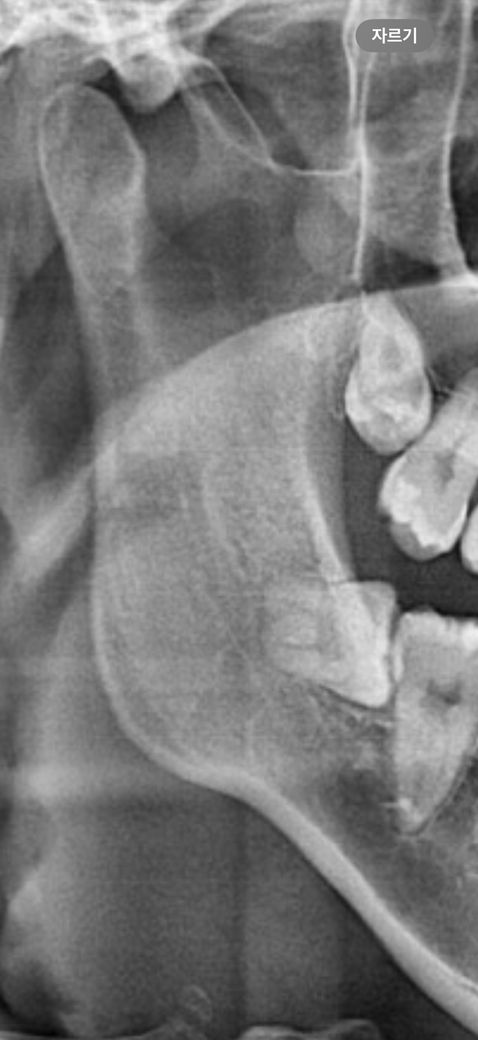

왼쪽 하악완전매복수평사랑니의 예상 난이도와 통증정도가 좀 궁금합니다

• 1번 째 사진

• 2번 째 사진

기울어져 있는 사랑니의 발치는 난이도가 높은 편에 속합니다.

또한 신경관이 가깝다면 발치의 난이도가 더올라가게 됩니다.

신경관에 가깝게 위치하고 있는 사랑니의 경우에는 상급치과병원에서 발치를 하는것이 좋을수 있습니다.